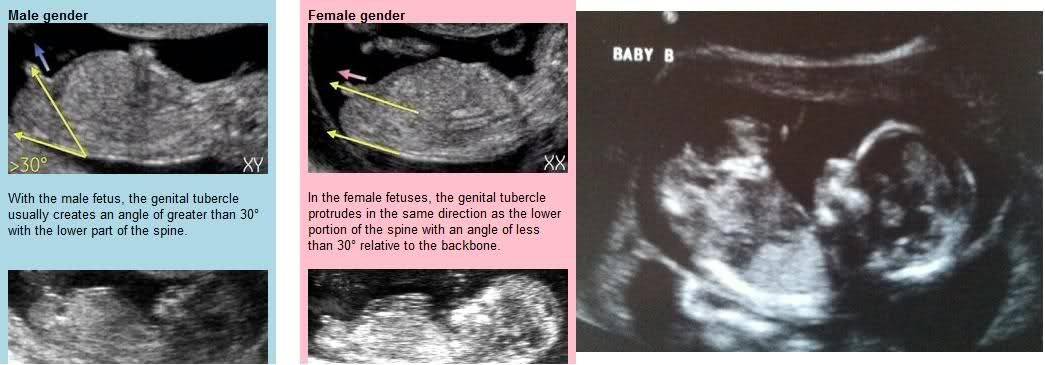

Пол на 14 неделе беременности по узи

Пол на 14 неделе беременности по узи 88 фото